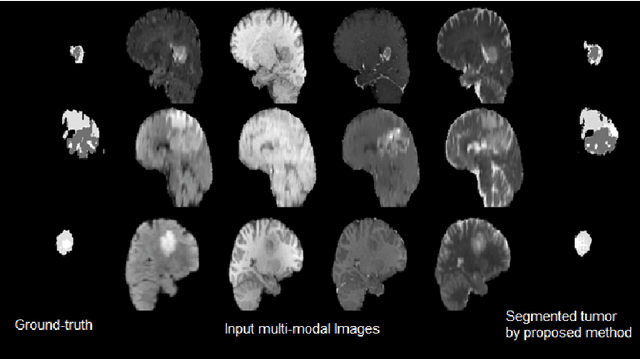

Abstract:Automated medical image analysis has a significant value in diagnosis and treatment of lesions. Brain tumors segmentation has a special importance and difficulty due to the difference in appearances and shapes of the different tumor regions in magnetic resonance images. Additionally, the data sets are heterogeneous and usually limited in size in comparison with the computer vision problems. The recently proposed adversarial training has shown promising results in generative image modeling. In this paper, we propose a novel end-to-end trainable architecture for brain tumor semantic segmentation through conditional adversarial training. We exploit conditional Generative Adversarial Network (cGAN) and train a semantic segmentation Convolution Neural Network (CNN) along with an adversarial network that discriminates segmentation maps coming from the ground truth or from the segmentation network for BraTS 2017 segmentation task[15, 4, 2, 3]. We also propose an end-to-end trainable CNN for survival day prediction based on deep learning techniques for BraTS 2017 prediction task [15, 4, 2, 3]. The experimental results demonstrate the superior ability of the proposed approach for both tasks. The proposed model achieves on validation data a DICE score, Sensitivity and Specificity respectively 0.68, 0.99 and 0.98 for the whole tumor, regarding online judgment system.